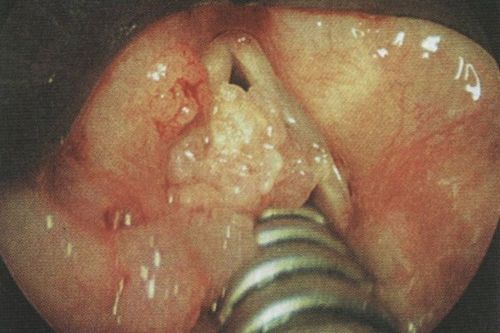

Для перевірки важко переглядаються області горла, гортані, голосового апарату, підстави мови, лікарі використовують інструменти (ларингоскоп або фарингоскопію).

Для деяких структур в горлі, які неможливо оглянути цими інструментами, застосовують гнучкі ларингоскопи і фарингоскопію. Вони проникають глибше, що дозволяє лікарю побачити поразку або відсутність папілом.

Лікар призначить біопсію для тих виростів, які виглядають підозрілими. Забір частинки папіломи роблять порожнистої голкою. Потім клітини розглядають під мікроскопом, щоб знайти або виключити рак.

Фото операції з видалення папилломатоза в горлі

Видалення папілом роблять звичайним скальпелем, випалюють лазером, рідким азотом і електричним струмом. Метод видалення залежить від віку пацієнта, локалізації папілом і можливостей лікарні.